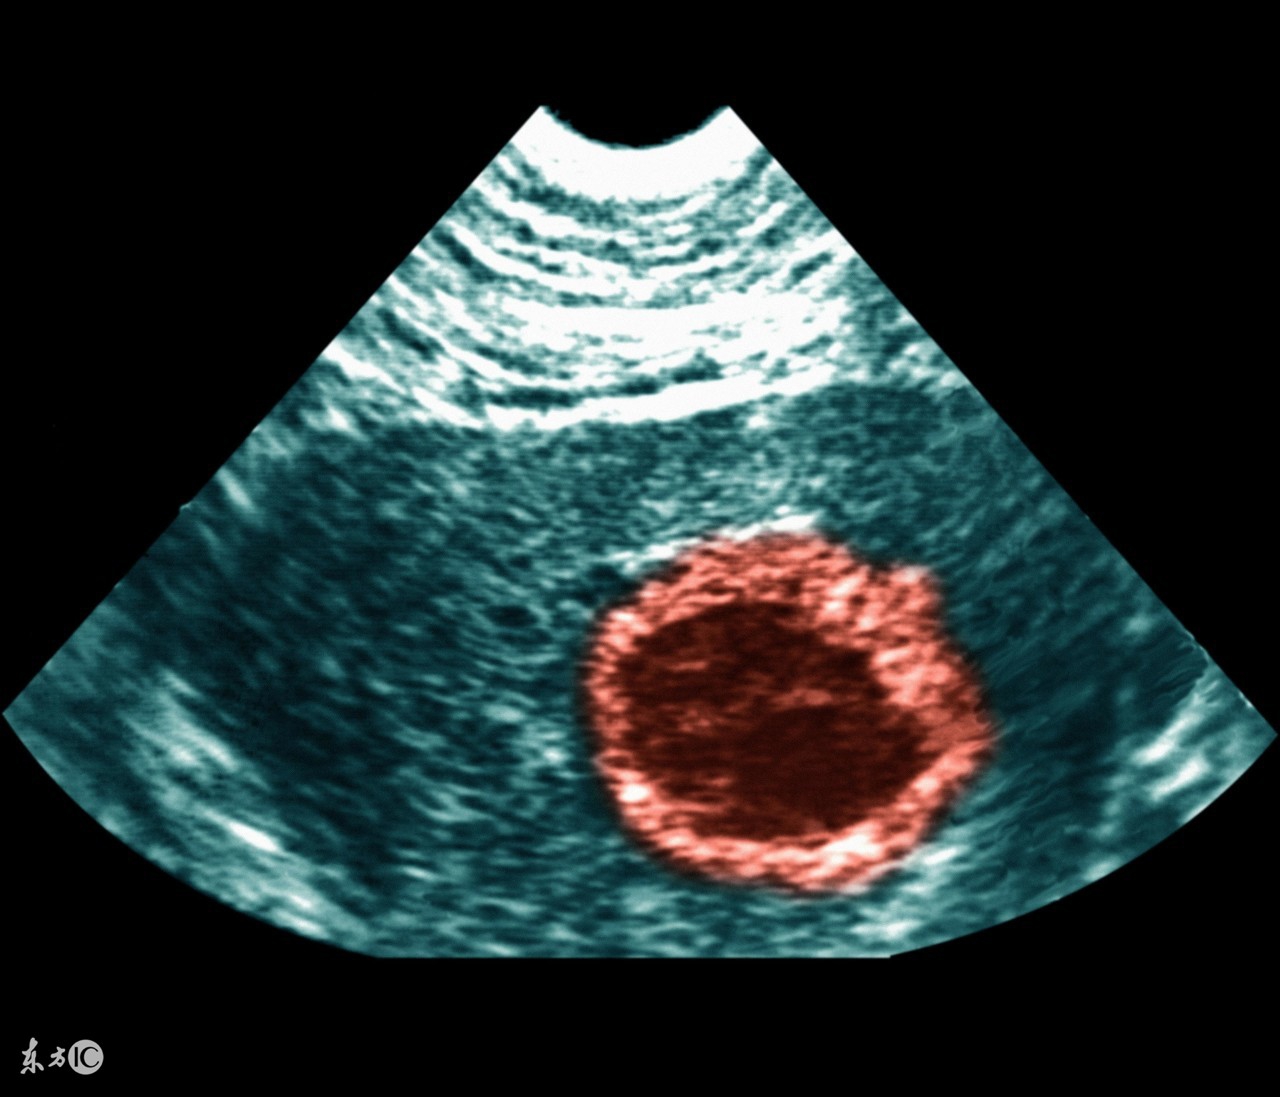

3、葡萄胎。

葡萄胎的问题相对并不是很常见,很多出现葡萄胎问题的女性朋友在停经后会发生断断续续的阴道出血,但是还会有比较明显的妊娠反应,有些朋友检查的时候会发现子宫增大的比较异常,这个时候就要考虑葡萄胎的可能性。建议最好能具体进一步检查hcg水平及B超等来确诊是否出现葡萄胎的问题。